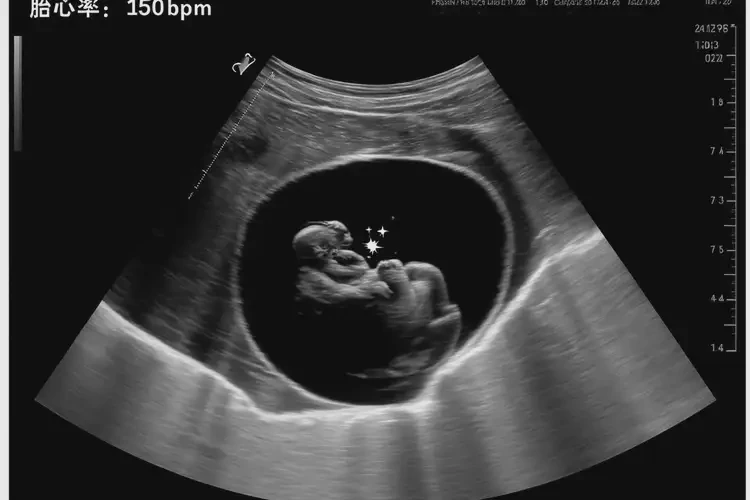

懷孕第4周胎心率91還能保住嗎(圖1)